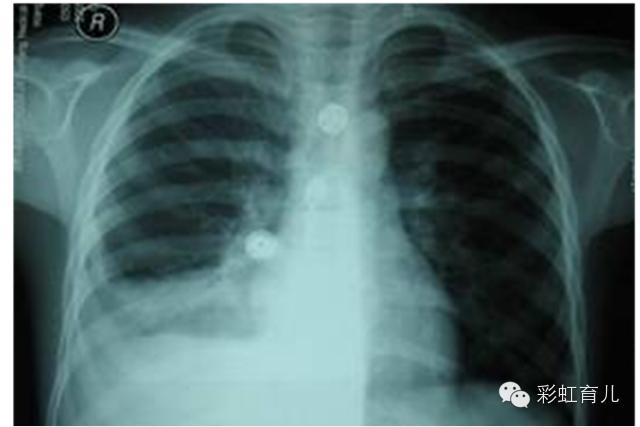

4.肺炎

临床表现

1、发热

2、咳嗽,较频繁

3、气促

4、全身症状

体征:

1、呼吸增快、40-80/分

2、鼻翼扇动和三凹征

3、肺部啰音

5.重症肺炎

1、缺氧 口唇甲床发绀、恶心、呕吐

2、面色苍白、烦躁不安

3、精神萎靡、烦躁或嗜睡、惊厥